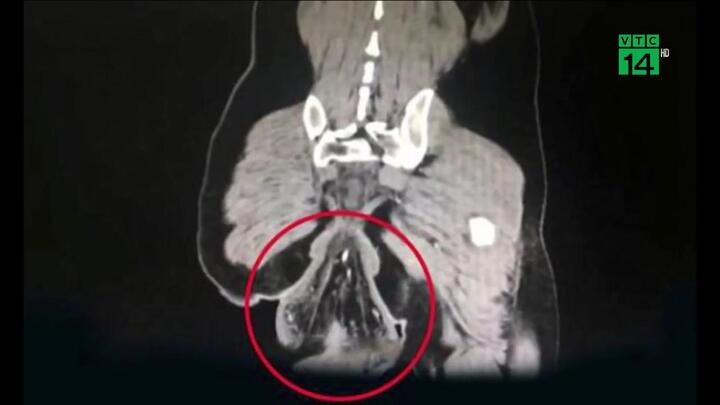

Người đàn ông Trung Quốc được đưa tới bệnh viện vào lúc nửa đêm trong tình trạng sa trực tràng nghiêm trọng sau khi chơi game trên điện thoại liên tục 30 phút khi đi vệ sinh.